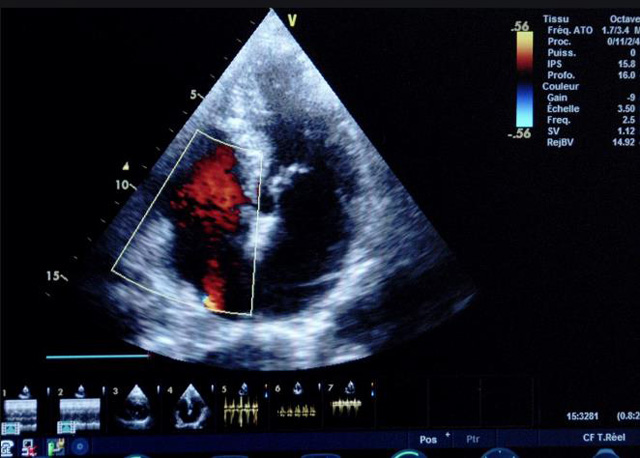

二、彩色室壁運動分析

(一)基本原理彩色室璧運動分析,從整體散射數據中識別心內膜邊界,并與前一幀彩色不同,心臟收縮或舒張期開始到結束時心內膜的全部過程。每一次順序顯示結束后,原來的彩色自動消失,以便進入下一個顯示過程。其結果是獲得對應于每一個心動周期的彩色顯示,描繪特定周期內室壁運動的時間運動軌跡。

(二)操作步驟根據背向散射數據中將心內膜運動的位移過程分類為組織或血液的原理,邊緣檢測跟蹤心內膜和血液的界面。橙色表示收縮期的開始,收縮期不同時相逐幀顯示色彩均疊加在收縮末期最后一幀圖像中。檢查時,可按以下步驟進行:

①顯示較為理想的二維圖像,常用切面有心尖四腔心、二腔心、左心室長軸和左心室乳頭肌水平短軸切面。

②啟動AQ系統,啟動后適當地調節增益補償,顯示心內膜。

③啟動CK系統,啟動后劃定感興趣區域。同時記錄的心動圖R波頂點為舒張末期,T波終點為收縮末期,顯示RT間期的CK彩階圖,連續記錄3~ 5個心動周期。